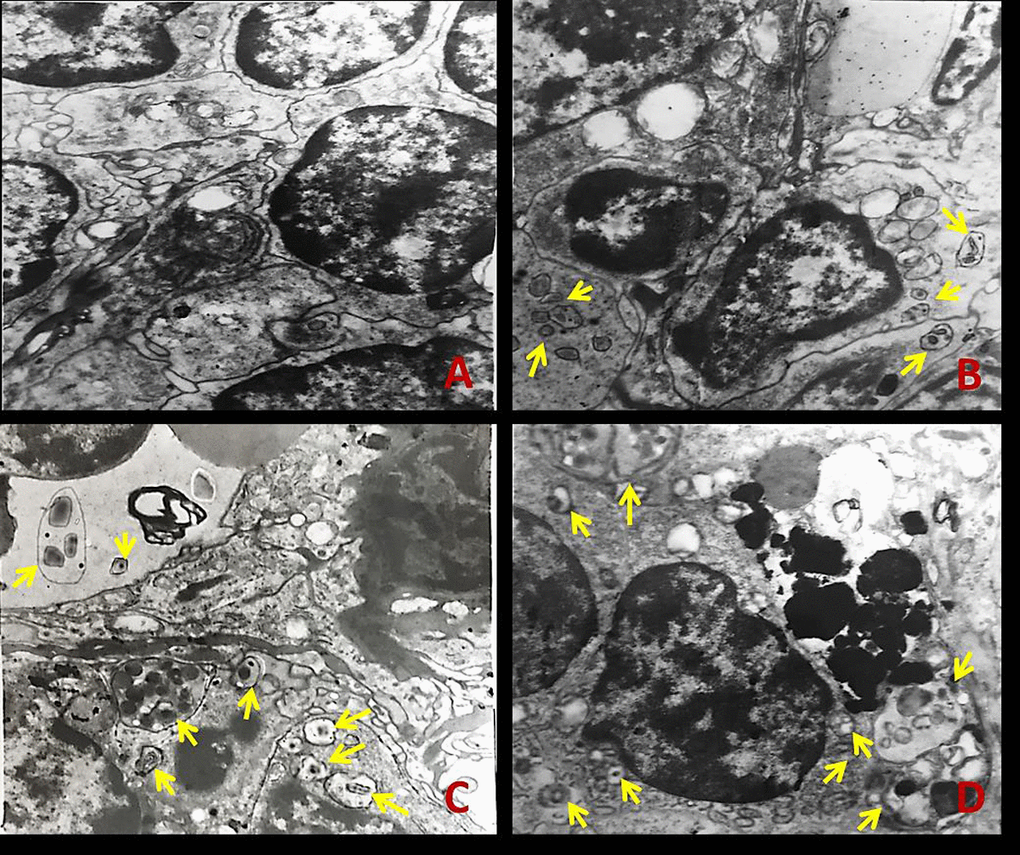

The splenic ultrastructure determined by TEM (Figure1) demonstrated that numbers of autophagosomes or autolysosomes were distinctly increased in NaF-treated groups when compared to the control group at 42 days of the experiment (Figure 1B-1D).

Figure 1. The ultrastructure of spleen tissue by transmission electron microscopy (TEM) at 42 days of the experiment. The yellow arrows represent autophagosome or autolysosome. (A) Control group; (B) 12 mg/kg group; (C) 24 mg/kg group; (D) 48 mg/kg group.

The appearance of autophagic vacuoles can be confirmed the occurrence of autophagy [20]. Once the autophagosome is formed, it must deliver its cargo to the lysosome in mammals or the functionally related vacuole in yeast and plants [34]. Then the outer membrane of autophagosome will fuse with lysosomal/vacuolar membrane to form the autolysosome [35]. Subsequently, the autophagic cargo are degraded and the component parts are exported back into the cytoplasm through lysosomal permeases for use by the cell in biosynthetic process or to generate energy [36]. We have observed that NaF caused an increase in the number of autophagosomes and autolysosomes in the mouse spleen (Figure1), which indicated that NaF induced autophagy in the spleen.